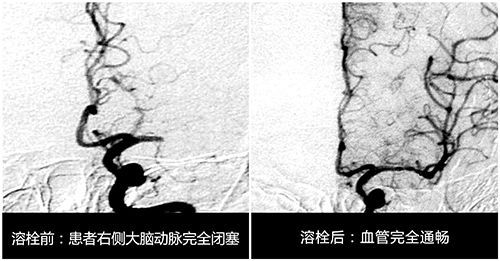

孙主任对急性脑梗死溶栓治疗进行了深入的研究,也是当时国内率先开展溶栓研究最早的专家之一。自1995年NINDS研究以后,美国、欧洲、加拿大等国将溶栓治疗超急性期缺血性卒中纳入脑血管病治疗指南,这种方法大大提高了梗死患者治疗的有效性及预后,这鼓舞着孙晓江朝着这个方向继续研究,他也多次参加国际神内学会会议,以撷取先进的理念和方法。

为了更好的进行研究他建立了自己的早期团队,是由他所带的研究生组成。据孙主任介绍,进行溶栓研究的要求是非常严格的,从溶栓治疗患者的选择,到治疗后并发症的预防,再到溶栓治疗的评估,以及影像学诊断与疗效评估,他都建立了一整套体系标准,并要求学生严格按照标准执行,其中最重要的一点是尽可能在“4.5黄金时间窗”内进行溶栓治疗。

1996年11月某天,65岁的张阿姨突发脑梗死,来院时张阿姨脑梗死已病发3—4小时。“当时患者脑梗死情况还是比较严重的,虽然她的意识还算清醒,但右侧肢体已经偏瘫,上肢和下肢的肢体肌力评分几乎为零级,手脚当时一点也不能动,如果不及时进行有效救治,患者不仅会右侧身体偏瘫,还可能会危及生命。”孙主任介绍说。

面对如此紧急的时刻,孙主任第一时间安排患者进行相关检查,随后根据患者的病症及检查结果进行了严格的评估,确定患者符合静脉溶栓的要求。紧接着对患者进行溶栓治疗,经过半小时的精心溶栓后,患者的肢体竟都能动了,病人和家属当时激动得千恩万谢。